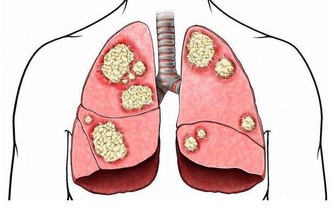

(12)關注身體異常變化

英國一項研究發現,在身體已出現異常症狀的患者中,提前3個月看醫生的人不足60%。早就醫、早診治是延長壽命的重要環節。

癌症就有一些徵兆,例如不明原因的體重驟減、高燒、極度疲勞、大小便習慣改變、異常出血、黑痣顏色和形狀異常、舌頭顏色異常等。